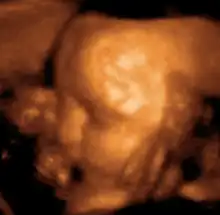

医学超声检查(英語:)是一种基于超音波的医学影像诊断技术,与其相关的学科称作超音波诊断学。超声检查使肌肉和内臟器官等軟組織可视化,包括其尺寸、结构和病理学。在产科中,超声检查广泛用於妊娠时的產前診斷。

盆腔超声是多囊卵巢综合征的主要诊断工具,也可用于子宫、卵巢和膀胱的成像。妊娠时超声用于检查胎儿的发育情况。男性也可进行盆腔超声检查膀胱和前列腺的健康状况。盆腔超声检查有两种方式:经皮和腔内。腔内超声可经阴道(女性)或者经直肠(男性)。

美国FDA警告说,实验室研究表明诊断水平的超声波会对组织产生物理效应,例如机械震动和温度升高。FDA建议,公众如无必要,不要随便暴露在超声波下,尤其是孕妇。尽管没有证据表明超声波想物理效应会伤害胎儿,但绝不可认为其能量对胎儿完全无害。并且FDA不许可利用医学超声波成像设备进行胎儿写真、影像留念等非医学用途行为,同时将医学超声波成像设备列为处方设备。[3]